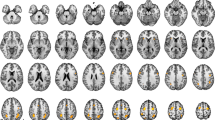

In this study, we measured primary motor cortex (MI) activity during a reaction time task to examine the appearance of MI activity that synchronized with the stimulus presentation (stimulus synchronous MI activity, SSMA). Because brain activity was expected to be enhanced by the repetitive/extensive activation, we hypothesized that the SSMA would be more clearly observable in athletes who were trained to perform reactive movements than in non-athletes. MI activity was measured in ten athletes and ten non-athletes by magnetoencephalography. The tasks were a simple reaction task and a Go/Nogo reaction task in which the subjects were asked to abduct their right index fingers in response to a visual stimulus. The Go/Nogo reaction time task was adopted to confirm the presence of the SSMA, because the MI activity in response to a Nogo stimulus did not overlap with the MI activity that was synchronous with the execution of the movement. The results show that the SSMA was clearly apparent in the athlete group (9/10). In the non-athlete group, however, only three subjects showed the SSMA (3/10). Moreover, the MI activity of the athletes tended to be larger than that of the non-athletes, even though the athletes did not specifically practice these index finger movements during their daily training. We concluded that long-term physical training promotes MI activity and the effects of reactive task repetition were more clearly apparent in the MI activity of the athletes.